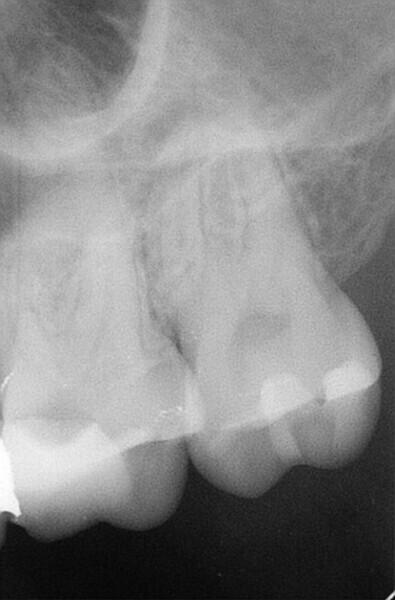

Endodontic treatment of maxillary left rst molar with complicated root canal system